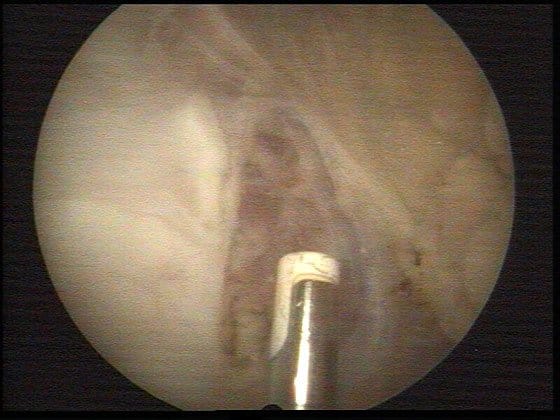

Sala Operacyjna

artroskopia201b